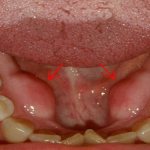

Пластика десны после имплантации передних зубов или формирование красивого десневого контура осуществляется при помощи абатмента (хотя обычно, если зуб находится вне зоны видимости, используется формирователь десны). Этот ортопедический компонент имеет округлую форму и диаметр, приближенный к диаметру будущей коронки. Протез будет установлен таким образом, что его нижнюю часть будет закрывать эстетичный десневой край.

2. протезирование: после того как имплант надежно прижился в кости (через 3-6 месяцев), можно приступать ко второму этапу – протезированию. Для этого на имплантат устанавливается абатмент – верхушка имплантационной системы, которая сначала будет выполнять функцию формирователя десны (чтобы вокруг будущей коронки был красивый и естественный десневой контур). Впоследствии абатмент будет опорой для коронки. Абатмент может быть как металлический (серый или золотой), так и белый диоксид циркониевый при высоких требованиях к эстетике. Далее снимаются слепки, и через несколько дней готовая постоянная коронка закрепляется на импланте.

• эстетические требования к передним верхним коронкам, поскольку они формируют улыбку.